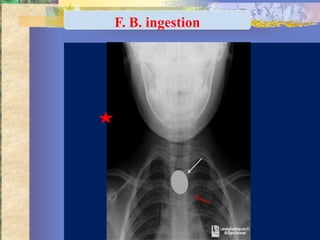

F. B. ingestion

Diagnosis …. ?

Retropharyngeal